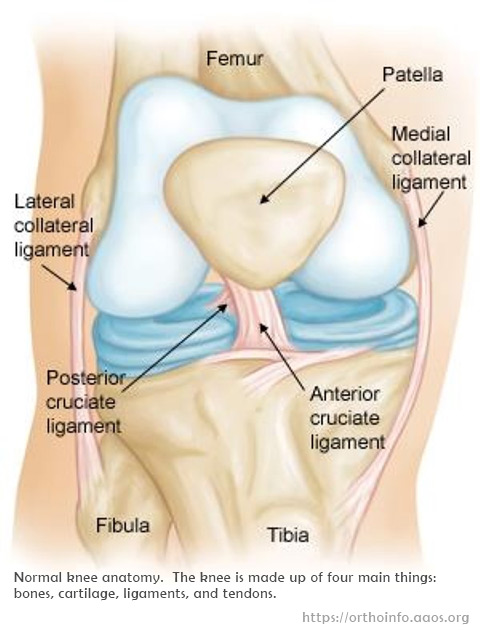

X光:

可排除骨折或有碎骨於關節內。

磁力共振:

診斷十字韌帶撕裂的準確率可超過九成,也可為其他膝組織如半月板受傷提供相關之資料。